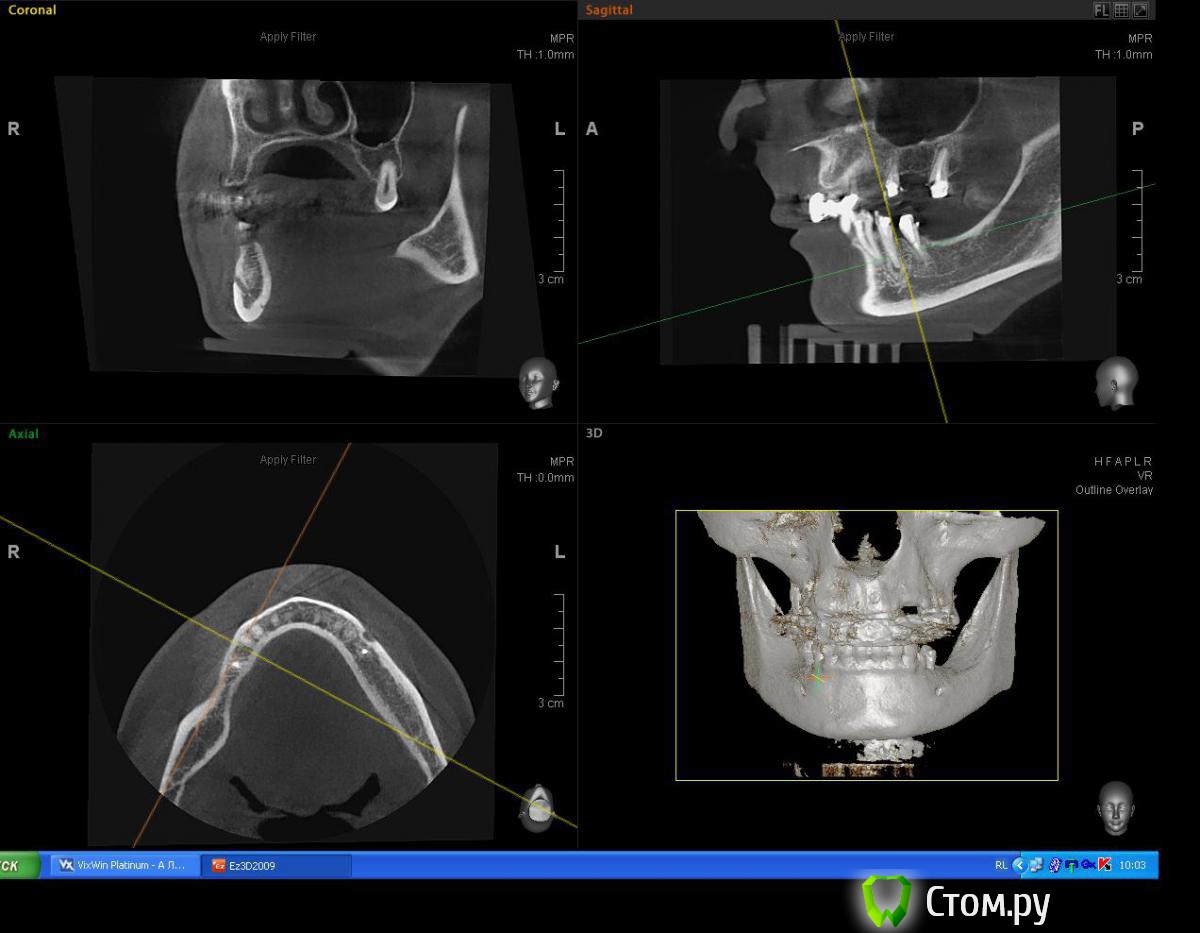

Mane Опубликовано 2 июля, 2014 Поделиться Опубликовано 2 июля, 2014 Для первичной фиксации вам неоходимо хотя бы 3-4 мм нативной кости в заапекальном направлении. Судя по срезам, они имеются, однако вместе со срезами лучше делать промеры (длина, ширина, толщина) для полноценной идентификации. Так же можете создать вируальный имплантат с планируемыми размерами и оценить его положение на срезах. +1 скорее всего вам будет достаточно 38х10 3 Ссылка на комментарий